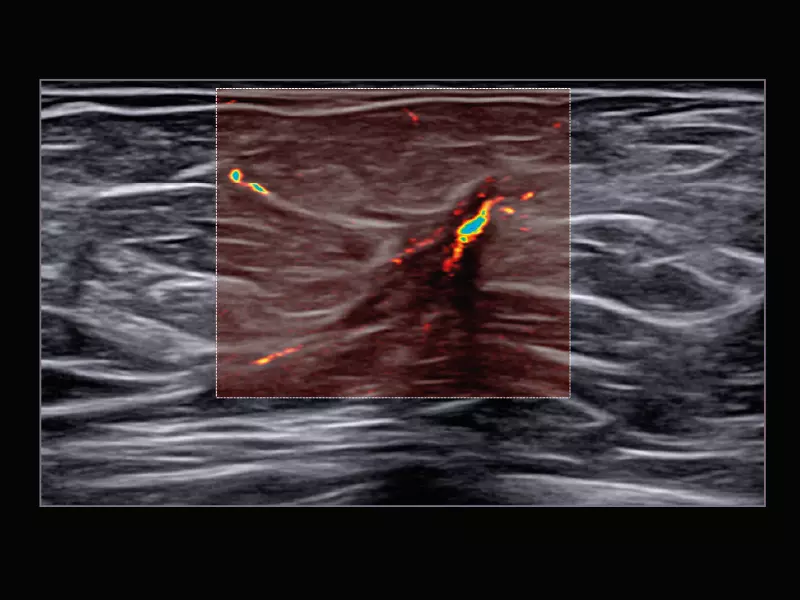

MyLab™C25 - MICRO-V-thyroid-linear

MyLab™C25 - MICRO-V-thyroid-linear